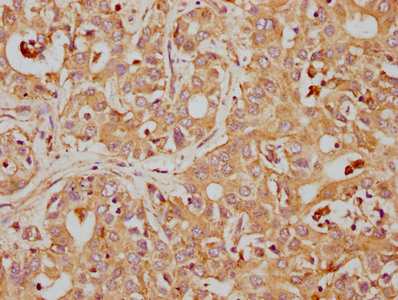

• IHC image of CSB-RA004950A0HU diluted at 1:155 and staining in paraffin-embedded human liver cancer performed on a Leica BondTM system. After dewaxing and hydration, antigen retrieval was mediated by high pressure in a citrate buffer (pH 6.0). Section was blocked with 10% normal goat serum 30min at RT. Then primary antibody (1% BSA) was incubated at 4℃ overnight. The primary is detected by a biotinylated secondary antibody and visualized using an HRP conjugated SP system.